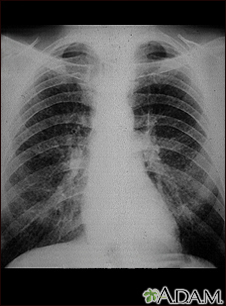

Coal worker's lungs - chest x-ray

This chest x-ray shows coal worker's lungs. There are diffuse, small, light areas on both sides (1 to 3 mm) in all parts of the lungs. Diseases that may result in an x-ray like this include: simple coal workers pneumoconiosis (CWP) - stage I, simple silicosis, miliary tuberculosis, histiocytosis X (eosinophilic granuloma), and other diffuse infiltrate pulmonary diseases.